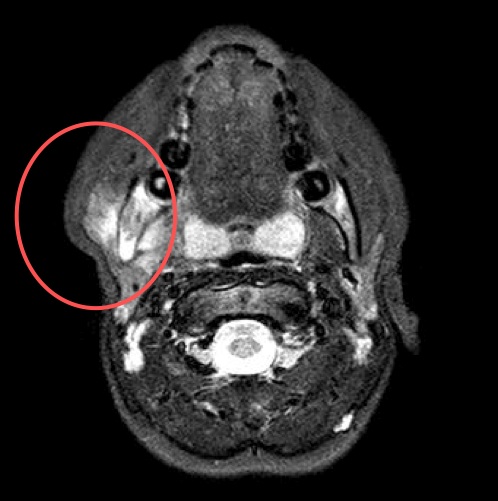

Dopo circa 2 mesi di remissione C. ha ricominciato a presentare saltuario dolore alla caviglia sinistra, con incostante limitazione funzionale, per cui ha ricorso alla terapia antinfiammatoria al bisogno. Inoltre da alcuni mesi ricomparsa di dolore e tumefazione in sede mandibolare destra. Al controllo, per il persistere della sintomatologia, si decide di ripetere la RMN del massiccio facciale che conferma l�interessamento del massetere ed evidenzia un possibile coinvolgimento osseo (Figura 1). C. ha cos� eseguito una TC che ha mostrato un disomogeneo addensamento della trama ossea in corrispondenza della branca montante e dell�angolo mandibolare di destra con qualche areola con aspetto erosivo superficiale del profilo dell�osso, in parte sfumato (Figure 2 e 3). Gli aspetti clinico e radiologico hanno deposto per un quadro di tipo infiammatorio da osteomielite cronica asettica.

Figura 1. RMN del massiccio facciale.